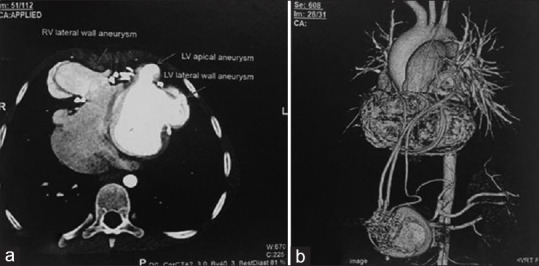

Cardiac strangulation is a rare phenomenon in children following epicardial pacemaker implantation, caused by compression of the heart and great vessels by the epicardial pacemaker wires. We report a rare case of cardiac strangulation presenting after 8 years of epicardial pacemaker implantation. On routine follow-up, computed tomography angiography showed significant extrinsic compression of the mid-left anterior descending (LAD) artery by the epicardial pacing wire. She was referred to our department for myocardial perfusion imaging (MPI), which showed significant inducible ischemia in the LAD territory. Following this, she underwent a successful pacemaker reimplantation. MPI can, thus, act as a good tool to assess the functional significance of the compression caused by strangulation of the heart by pacemaker leads in asymptomatic patients.